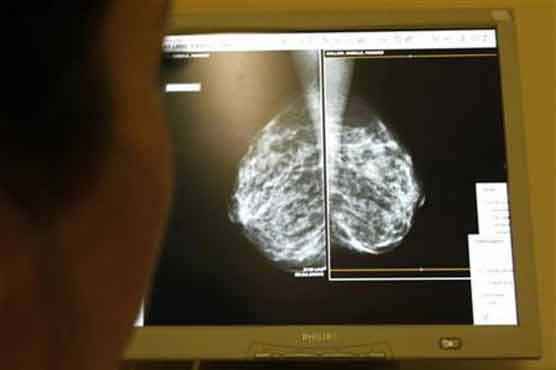

Summary Mammograms has not saved as many lives as women thinks, according to a new research.

Many women who have survived breast cancer often say it was a mammogram that “saved their life,” a powerful testimonial that can encourage other women to get regular breast cancer screening tests. But what are the chances that the test actually saved a womans life? Not that great, according to a new analysis published in the Archives of Internal Medicine on Monday.The numbers suggest that at most, 13 percent of those diagnosed with breast cancer have been helped. That means the other 87 percent have not been helped, Dr. Gilbert Welch of Dartmouth College, who led the study, said in a telephone interview. That is important when we keep hearing these stories from breast cancer survivors, he said.Welch said women who tell their stories about surviving breast cancer can be a powerful inducement for other women to get tested for breast cancer, and as mammogram technology has improved, the chances are even greater that doctors will find something suspicious. But early detection for some women may not be much of a benefit, especially if a cancer is slow growing, Welch and colleagues say. And many women may be diagnosed and treated for a cancer growing so slowly it might never have caused any symptoms or threatened their lives.The findings add new fodder to the simmering debate over the benefits of screening healthy people for cancer. Earlier this month, the government-backed U.S. Preventive Services Task Force recommended that healthy men not get a common blood test for prostate cancer, causing an uproar among cancer specialists who fear more men will die from prostate cancer. And in 2009, the same group recommended that women under 40 not get a mammogram and that women 50 and older get the test only every other year, rather than yearly, causing an outcry from breast cancer advocacy groups.But screening tests have both benefits and risks, says Welch, who views the current debate as positive for patients who are starting to think more about the risks of screening.An earlier study by Welch found that routine screening for prostate cancer has resulted in as many as 1 million American men being diagnosed with tumors who might otherwise have suffered no ill effects from them.In the latest study, Welch and colleagues looked to see how much mammography reduces deaths from breast cancer.